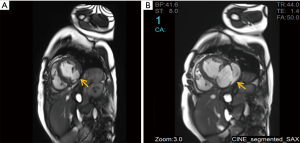

A 66-year-old woman was admitted to our center on June 2, 2018 with a confirmed diagnosis of AMI. She had undergone mitral valve replacement with St. Jude Medical E100-29M biological valve in 2012 due to mitral valve prolapse syndrome and severe mitral incompetence. Coronary angiography performed on the second day after her admission showed that the distal left circumflex coronary artery was completely occluded. Since the vessel was tine, no stent was implanted. Echocardiography revealed the presence of LVFWR and pseudoventricular aneurysm. Cardiac magnetic resonance imaging (MRI) performed on May 10 and May 31, 2018, revealed a giant pseudoventricular aneurysm located in the inferior and lateral walls of the left ventricle; the rupture diameter increased from 22 to 28 mm, and the maximum tumor diameter increased from 40.9 to 90.2 mm (Figure 1A,B). The patient developed discomforts such as orthopnea and anorexia, along with worsening symptoms. Blood biochemical tests showed her NT-proBNP was >35,000 pg/mL. Since the patient had become critically ill and her heart rupture had lasted 4 weeks, transcatheter closure under general anesthesia was performed on June 5. An incision was made to expose the left carotid artery (CA), and left heart ventricular angiography performed through the CA revealed the presence of a giant pseudoventricular aneurysm. The diameter of the rupture at the ventricle was about 30 mm. A CA-ascending aorta-left ventricle-pseudoventricular aneurysm track was established, and a 36-mm atrial septal occlusion device (SHSMA, Shanghai, China) was successfully placed. Left ventricular (LV) angiography and cardiac ultrasound were performed immediately after operation. It was found that the occlusion device was fixed to the LVFWR, and there was only a small number of residual shunts in the pseudoventricular aneurysm (Figure 2A,B).